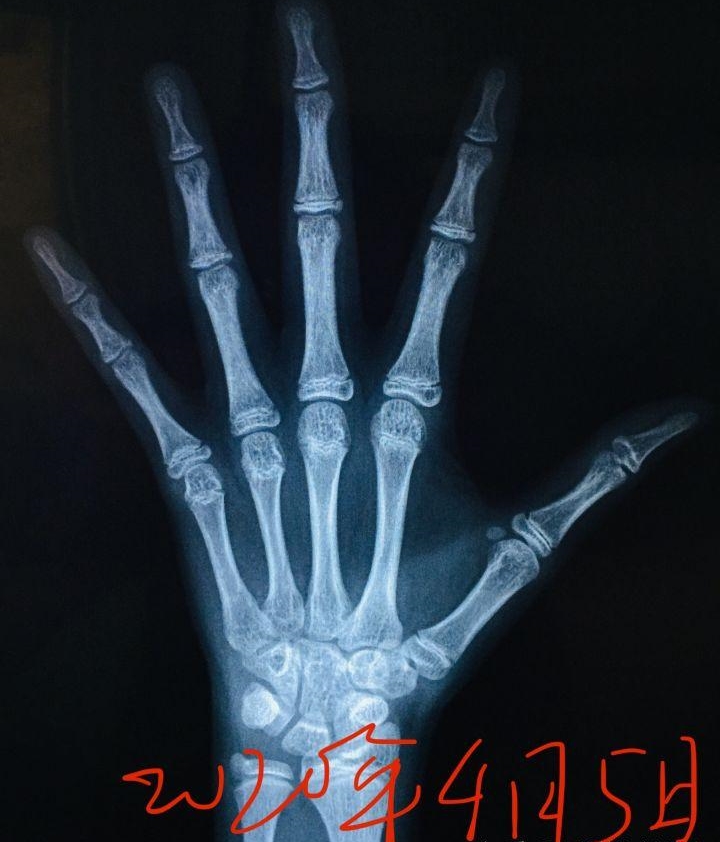

这个骨龄有多少?